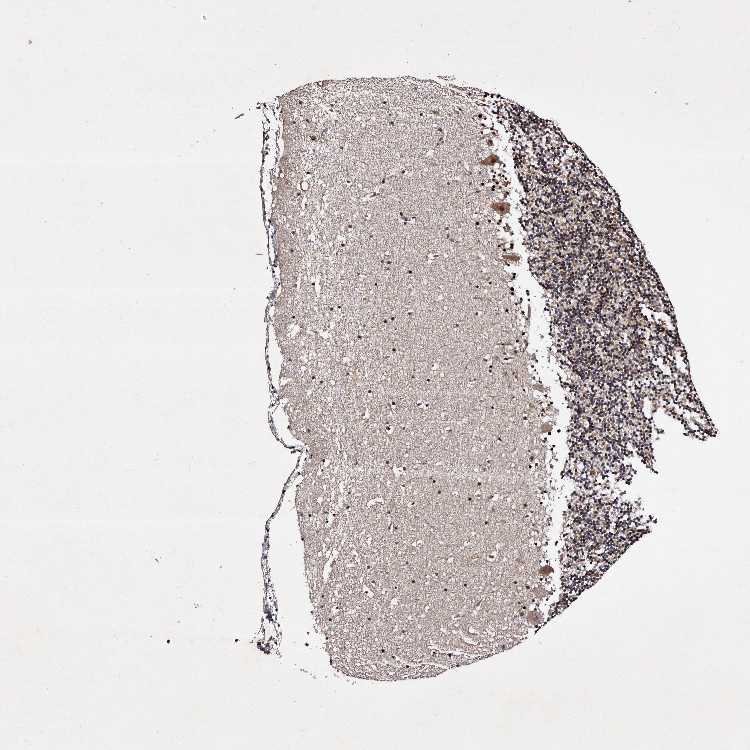

CEREBELLUM - Antibody stainingi

Antibody staining in the annotated cell types in the current human tissue is reported as not detected, low, medium, or high, based on conventional immunohistochemistry profiling in selected tissues. This score is based on the combination of the staining intensity and fraction of stained cells.

Each image is clickable and will lead to virtual microscopy that enables deeper exploration of all samples and also displays staining intensity scores, fraction scores and subcellular localization as well as patient and tissue information for each sample.

Antibody HPA025690

Purkinje cells Medium

Cells in granular layer Low

Cells in molecular layer Low